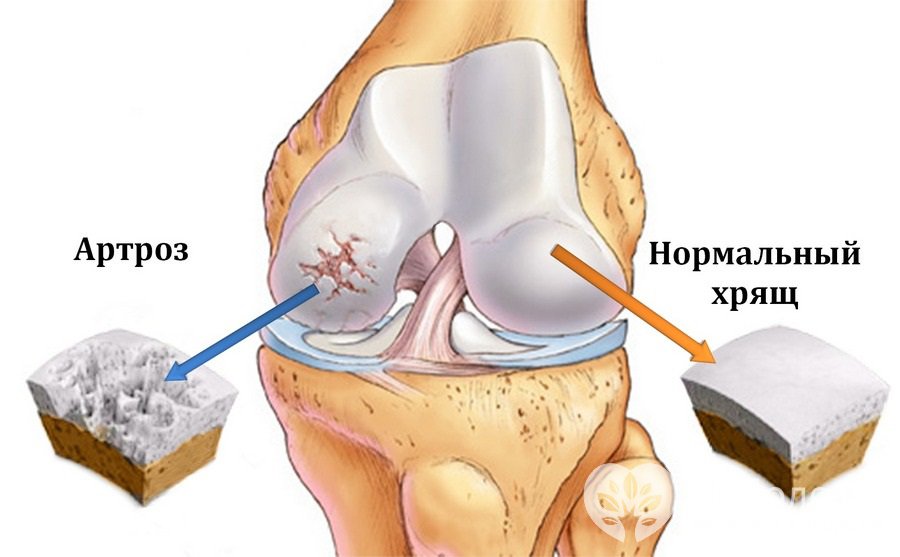

Артроз коленного сустава (гонартроз) – это хроническое дегенеративно-дистрофическое заболевание коленного сустава, которое характеризуется разрушением суставных хрящей, деформацией коленного сустава с последующим ограничением движений в нем.

Разрушение хряща при артрозе коленного суставаАртроз коленного сустава занимает первое место по распространенности в общей структуре артрозов. Заболеванию подвержены в основном лица старше сорока лет – в данной возрастной группе артроз коленного сустава чаще встречается у женщин, среди пациентов более молодого возраста преобладают лица мужского пола. Примерно в 6-7% случаев артроз коленного сустава приводит к инвалидности.

Коленный сустав образуется суставными поверхностями бедренной и большеберцовой кости. Передняя поверхность коленного сустава защищена надколенником (коленной чашечкой). Суставные поверхности бедренной и большеберцовой кости, как и задняя поверхность надколенника, покрыты плотноэластичным гиалиновым хрящом, толщина которого составляет 5-6 мм. При ударных нагрузках хрящ выполняет амортизирующую функцию, а при движениях уменьшает трение. У клинически здоровых людей процессы синтеза и разрушения хрящевой ткани находятся в равновесии, когда равновесие нарушается в сторону увеличения деструкции, развивается артроз. При артрозе коленного сустава в мелких внутрикостных кровеносных сосудах, питающих гиалиновый хрящ, нарушается кровообращение, вследствие чего поверхность хряща становится более сухой, а со временем утрачивает гладкость. На поверхности гиалинового хряща образуются трещины, что служит причиной регулярного микротравмирования хряща при движении. С прогрессированием патологического процесса хрящевая ткань истончается, суставная площадка расплющивается, адаптируясь к нагрузке. По краям суставных поверхностей возникают остеофиты, которые представляют собой костные выросты, формирующиеся по причине компенсаторного разрастания костной ткани. Патологический процесс захватывает синовиальную оболочку и капсулу сустава. Суставная жидкость становится более вязкой, хуже выполняет свои функции, что приводит к усилению деструктивных процессов в суставе. При дальнейшем прогрессировании заболевания хрящ истончается еще больше, на некоторых участках исчезает вовсе. Это приводит к резкому усилению трения между суставными поверхностями и деформации костей, образующих сустав. Коленный сустав деформируется, деформация может быть вальгусной, т. е. Х-образной, или варусной, т. е. О-образной. Движение в пораженном суставе ограничивается вплоть до полного исчезновения (формируется анкилоз – необратимое и полное разрушение сустава).